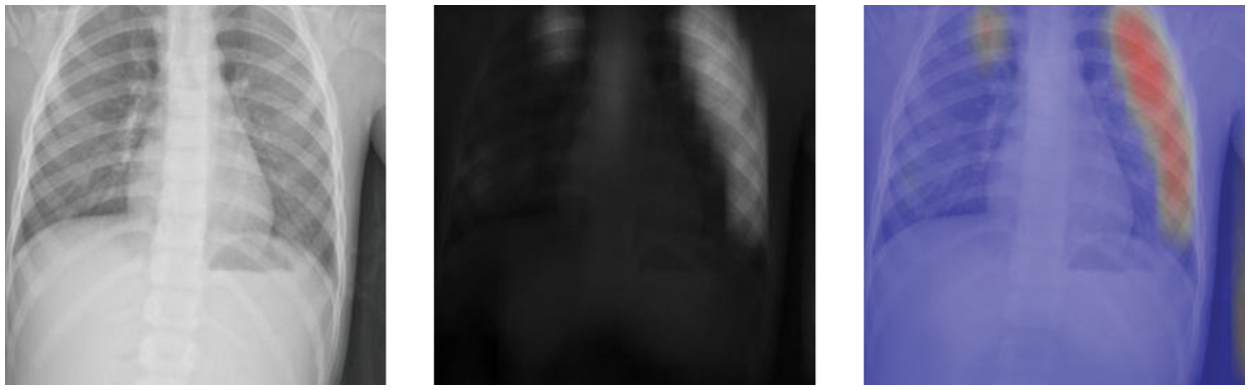

Fine-grained (FG) classification is a new paradigm in this field. The spirit of the fine-grained classification is to find the local information in images to expand the small differences between classes. Therefore, fine-grained classification can learn both the local and global features of the images, which are suitable for pneumonia diagnosis using chest X-ray images. As shown in Fig. 2, the local information of the chest X-ray image is located by using an attention mechanism. The attention mechanism finds the discriminative parts denoted as the attention maps and then fuses the attention maps and the raw images to locate the local parts denoted as the attention thermal map. As the attention mechanism can judge the significant parts in the images, the FG method can pay attention to these discriminative parts to train the CNN classifier while ignoring other irrelevant information and promote the classification accuracy of CNN models [9].

Figure 2: The images from the Chest X-ray 2017 dataset, from left to right, are the original raw image, attention map, and attention thermal map